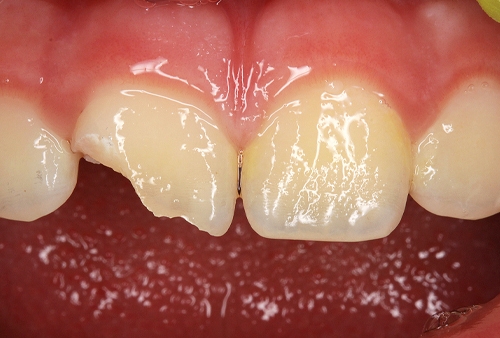

Daimi dişlərin travmatik zədələnmələri uşaq və yeniyetməlik dövründə olan şəxslərdə çox tez-tez rast gəlinir. Tac qırılmaları və lüksasiya travmalar içərisində ən çox rast gəlinənlərdir. Ancaq müxtəlif kliniki hallarda digər zədələnmə formaları da aşkar edilə bilir.